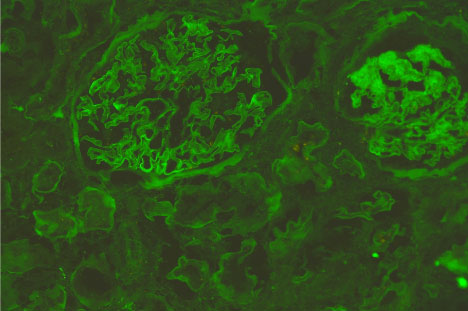

Figure 1 and Figure 2 show the immunofluorescence (IF) staining in two different cases; a case with mild IF, less than 25% of the tubules showing reabsorption proteins (Figure 1), and another case with severe IF, more than 50% of the tubules show reabsorption proteins (Figure 2).

Figure 1: Immunofluorescence micrograph of a renal tissue showing severe IF staining, more than 50% of the tubules show positivity for reabsorbed albumin in their lining epithelium. View Figure 1

Figure 2: Immunofluorescence micrograph of a renal tissue show negative tubular IF staining for reabsorbed albumin. View Figure 2